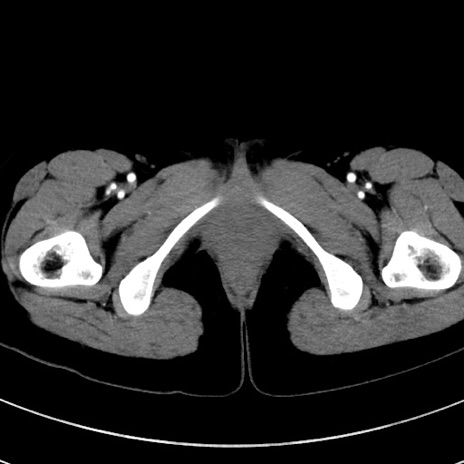

症例17(横断像)

【症例】20歳代女性

【主訴】嘔吐、下腹部痛

【現病歴】昨日夕食後に嘔吐し下腹部痛が出現。本日になっても嘔吐持続し改善しないため来院。

【身体所見】意識清明、BT 37.2℃、BP 108/67mmHg、腹部:平坦、やや硬、下腹部正中から右にかけて圧痛あり、反跳痛軽度あり、tapping pain(+)。

【データ】WBC 13600、CRP 14.94